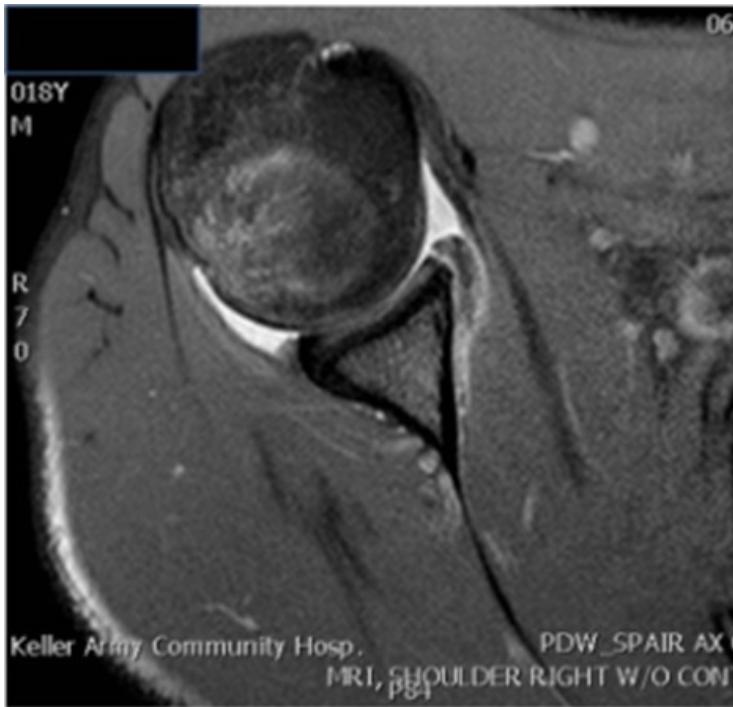

| Special Tests | Rotator Cuff Power (compare both sides): • Instability (Bankart): Apprehension Test (abduct and externally rotate arm, apply anterior pressure, watch patient’s face). • Supraspinatus (Empty Can Test): Flex shoulder to 30° with thumbs down; ask patient to resist. • Impingement tests: Neer’s Impingement Test, Hawkins’ Impingement Test. or neer’s rotator cuff + abduction resistance for supraspinatus • Infraspinatus: Ask patient to perform external rotation against resistance (elbows at 90°). • Subscapularis: Ask patient to perform internal rotation against resistance OR use the Lift-Off Test. • Teres Minor: Ask patient to perform external rotation against resistance in 90° of shoulder abduction. • Biceps Tendon: Speed’s Test (resisted shoulder flexion with elbow extended and supinated) OR Yergason Test. • Deltoid: Axillary nerve assessment: Motor (active abduction - then drop test- Deltoid), Sensory (upper lateral aspect of arm). Serratus Anterior - Scapular Winging; long thoracic nerve: push against wall - observe back • AC Joint: Cross Body Adduction Test. • Muscle power tests: Abductors/Adductors, Internal/External Rotators, Serratus Anterior (winging), Biceps Brachii. | Apprehension test: Neer’s Impingement Test: Yergason Test: External / Internal Rotators Strength Test: Supraspinatus Test: Serratus Anterior - Scapular Winging; long thoracic nerve: Biceps Tendon & Ruptured long head: ![]() |